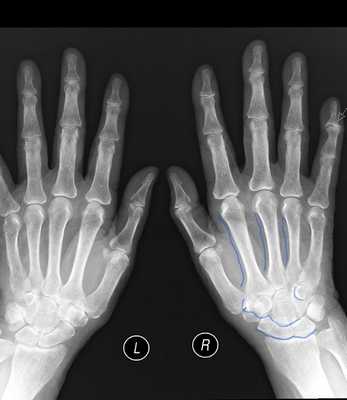

Поражение кожи и подкожной клетчатки. Определяются лентиго тела и головки полового члена, возможно увеличение полового члена, а также подкожные липомы. Липомы у детей встречаются крайне редко и их сочетание с макроцефалией позволяет заподозрить данный синдром.

Обнаруживаются, как правило, множественные подкожные липомы. Кроме того, выявляются множественные кожные сосудистые мальформации, которые могут быть врожденными, но чаще возникают после 3 лет. Они представлены подвижными кожными или подкожными узлами диаметром от 0,5 до 2 см, обычно коричневато-фиолетовой окраски, иногда болезненными.

Узлы чаще располагаются в области брюшной стенки, кистей, стоп и бедер. При гистологическом исследовании обнаруживаются мальформации смешанного типа (капиллярного, венозного и, возможно, лимфатического). Спонтанная инволюция этих образований не наблюдается. Иногда отмечаются внутричерепные сосудистые мальформации. Иногда встречается лимфедема нижних конечностей.

Клиническое наблюдение о сочетании лентигиноза полового члена и мошонки с липомой, сосудистой мальформацией и поражением внутренних органов представлено ниже.

Назначена заместительная терапия L-тироксином в дозе 100 мг и кальций Д3-никомед 1 табл. утром. В период данной госпитализации были диагностированы лентигиноз полового члена и мошонки, липома правой подмышечной области, сосудистая мальформация в области брюшной стенки слева и очаговый фиброз в S2—S6 правого легкого без нарушения функции дыхания.